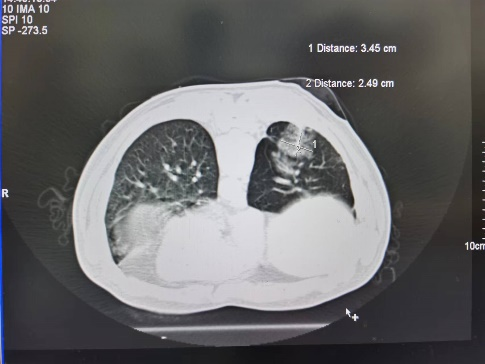

51岁的辛先生和74岁的汪女士均为我院胸外科的肺癌术后随访6年的老患者,辛先生在上月体检时行胸部CT检查发现自己的右侧肺部竟再次长出一个直径约1.5cm的混合磨玻璃结节,而汪女士在近1年来出现右侧胸腹壁疼痛症状,复查胸部CT及骨扫描发现肋骨及胸椎癌转移。出现新发结节令辛先生寝食难安,查出骨转移更是令汪女士惶恐失措。为寻求治疗,两位患者再次来到我院胸外科李少民教授处就诊。

考虑到两位患者均经历过手术的疼痛及术后化疗的折磨,本次治疗旨在消除病灶减轻患者痛苦,提高生存质量。为此,经过详细地评估及充分地沟通后,李少民教授为患者制定了“冷冻消融”的治疗方案,其中辛先生的病灶位于肺野外围适合CT引导下冷冻消融,汪女士的病灶位于肋骨及椎体,更适合超声引导下冷冻消融。

经过周密术前准备后,由胸外科李少民教授、马跃峰副主任医师、马震川主治医师,在放疗CT定位室、超声科的严密配合下为两位患者分别实施了CT引导下、超声引导下的肿瘤冷冻消融术。经过反复地定位及精准地穿刺,团队顺利将冷冻消融针置入肺结节中,经过重复2个循环的“冷冻-复温”,肿瘤经冷冻消融后变成了“冰块”。手术历时约半个小时,患者反应良好,没有明显疼痛及胸闷气短。